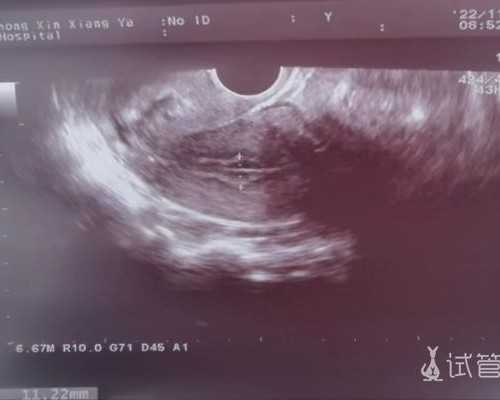

1、检查身体费用:台北做试管婴儿之前,医生会安排做一个不孕不育方面的检查,从而判断夫妻双方是否能做试管以及是否存在影响试管婴儿成功率的疾病。若发现疾病,可及时采取措施解决。

2、促排卵费用:进入试管婴儿周期以后,医生会采用促排卵药帮助患者达到排多个卵细胞的目的。促排药有国产和进口的,两者的费用差别较大。

3、试管婴儿手术费用:包括了实验室受精、培胚以及之后的胚胎移植费用,需要注意的是,受精方式有传统的受精方式和单精子细胞注射技术,医生会根据夫妻双方的情况决定采用哪种技术,不同技术的费用是不同的。这个试管家庭需要清楚。

4、影响试管婴儿的疾病治疗费:部分女性患有影响试管成功率的疾病。比如宫腔粘连、慢性盆腔炎等疾病,需要先做一些额外的治疗,再进行试管婴儿手术。

5、剩余胚胎的冷冻费用以及移植后补充黄体酮的费用。